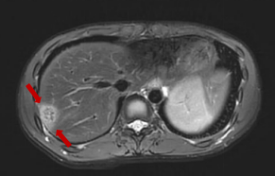

磁共振显示:肝右叶包膜下见多处团片状、楔形病灶,大者位于S7段,范围约2.7cm×1.8cm,部分病灶内见门静脉穿行,门脉血管无阻塞或异常征象,边界欠清。提示:肝右叶包膜下多发异常信号。